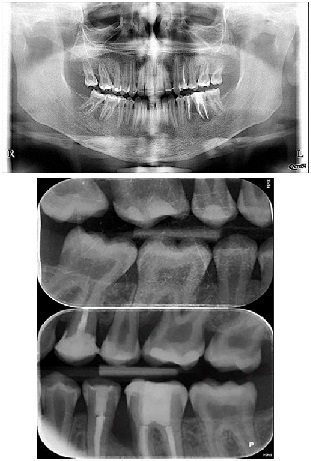

Periapical radiography (phosphorus number 2 plaque and X-MIND® Unity; Acteon) and cone-beam computed tomography (X-MIND® 3D; Acteon) (80 × 80, 150 Micron) were performed and showed periapical lesions on teeth 14, 15, 16, 24, 25, 26, 35, 36, and 46, as well as advanced endo-perio lesions on teeth 26 and 16. orthopantomogram (X-MIND® 3D; Acteon) and bitewings (phosphorus number 2 plaque and X-MIND® Unity; Acteon) also showed wide pulp chambers and roots canals. Figure 1, Figure 2

Figure 1.1 and 2 show a wide pulp chamber, root canals, and several restorations.

Figure 2.2. 3, 4, and 5 show periapical lesions on teeth 15, 16, 24, 25, 26, 35, 36, and 46.